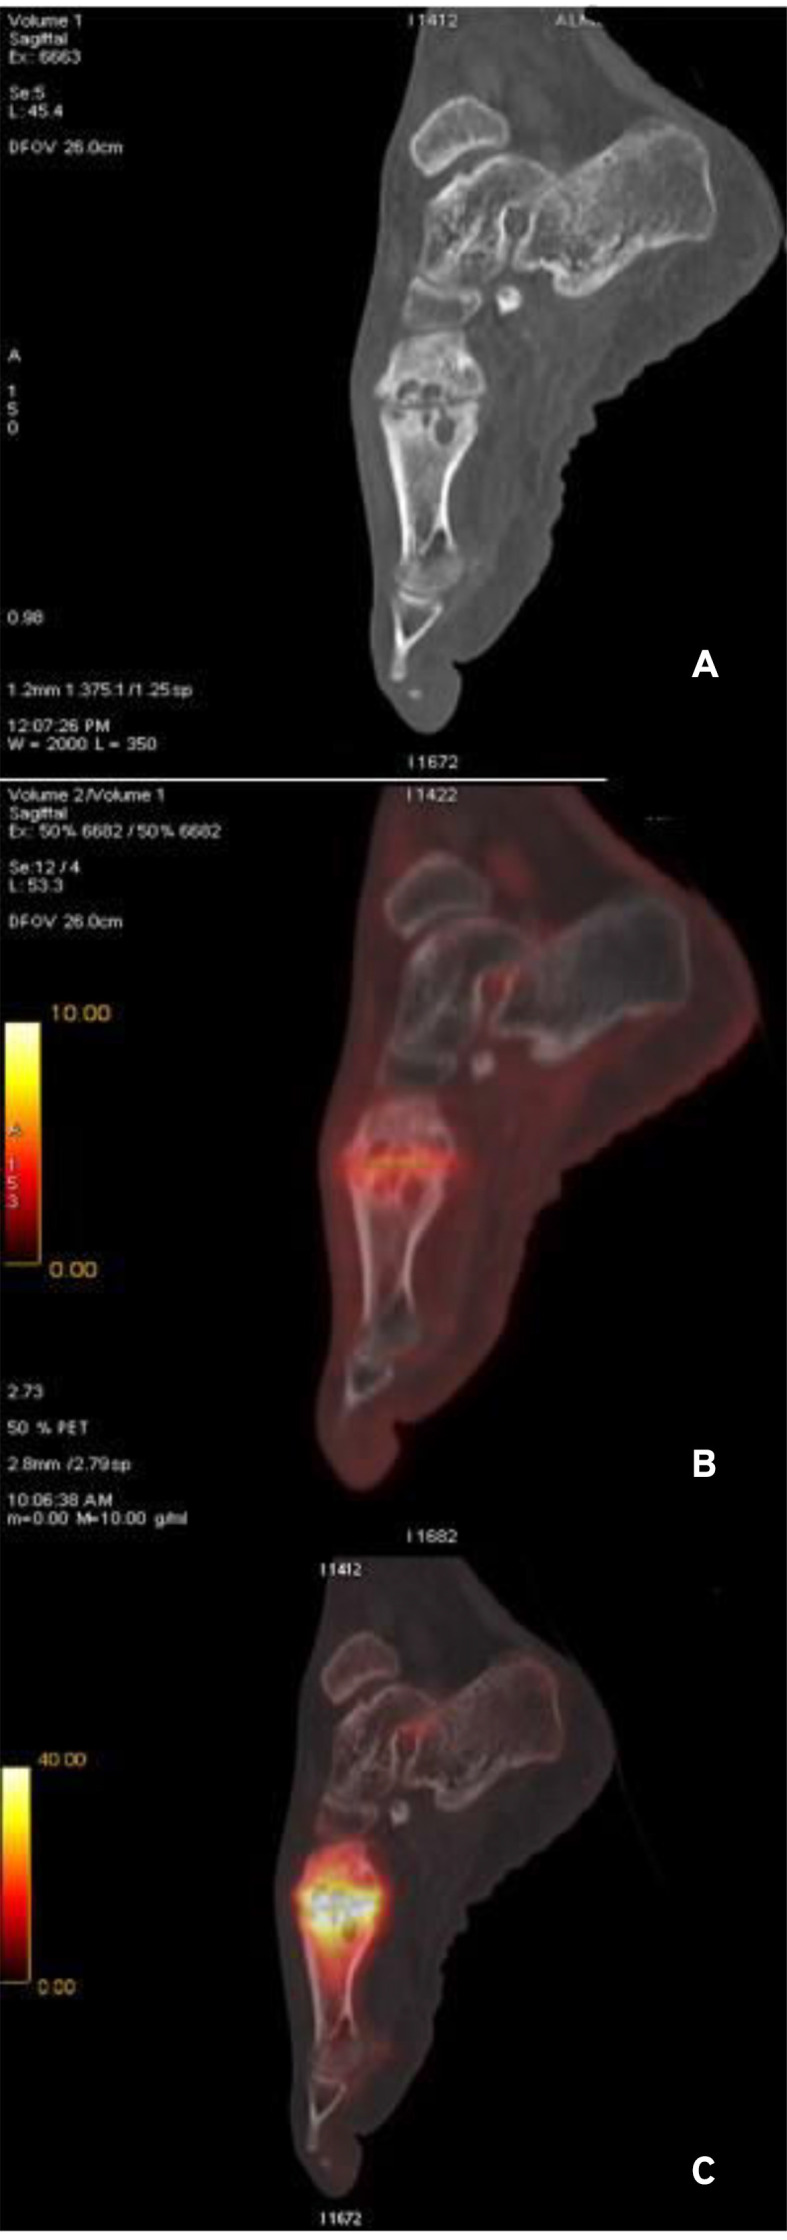

Increasingly Charcot neuroarthropathy (CN) is being recognized in patients with Charcot-Marie-Tooth (CMT) disease. In this report, we describe a case of CN in a CMT patient, adding to the very scarce literature describing this association. We additionally report his unique evaluation with fluorodeoxyglucose (FDG) and sodium fluoride (NaF) positron emission tomography/computed tomography (PET/CT) scanning, the study of which is limited in CN despite its promising role. A 54-year-old known case of CMT, presented with left foot pain, and swelling for 4 months. Weakness and sensory deficits as a result of CMT were evident in both lower and upper limbs. His x-ray was suggestive of CN. Both FDG and NaF PET/CT scanning demonstrated increased tracer uptake in the first tarsometatarsal joint (TMTJ), in keeping with CN. Recognition of the association of CMT with CN is of vital importance as early diagnosis relies on high clinical suspicion. Characterizing risk factors of CN in CMT patients is still under study. Moreover, there is lack of data evaluating the role of PET/CT in CN and specifically in the context of CMT.